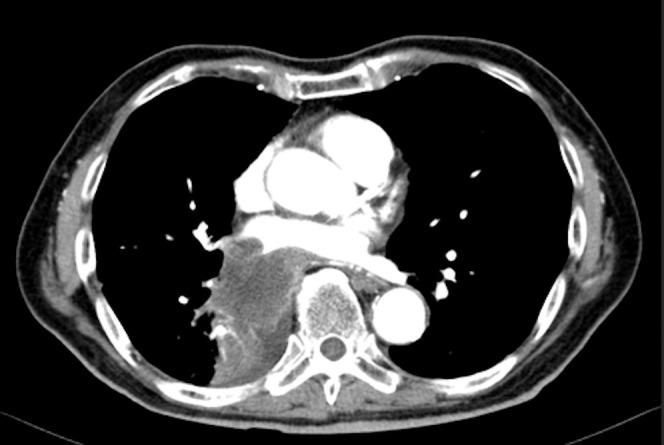

Basilar artery occlusion (BAO) accounts for only 1% of all strokes, and cerebral infarction resulting from tumor emboli has been infrequently demonstrated; therefore, few reports described BAO due to tumor embolus and its treatment experience. We report here an 83-year-old man with an acute BAO caused by embolized lung tumor invading right pulmonary vein that was revealed as metastasis of prostate adenocarcinoma. The patient underwent rapid recanalization through acute thrombectomy with a direct aspiration first pass technique (ADAPT) with Penumbra catheter. Successful recanalization was achieved in reperfusion grade of thrombolysis in cerebral infarction (TICI) 2b, and the embolus revealed a highly elastic hard tumorous mass of which texture was too tough to be caught by stent retriever. Immunohistopathologic examination of the embolus revealed adenocaricinoma of the prostate. In spite of that the recanalization was obtained, the patient died of the brain stem infarction after 7 days from the onset. We experienced a rare case of acute BAO caused by embolized prostate cancer metastasizing lung and invading pulmonary vein. When we face to patients with lung tumor invading pulmonary vein, tumor embolus should have been strongly considered and aspiration thrombectomy may be safer and more effective for the condition because of the difficulty of predicting an embolus's texture before treatment.

基底动脉闭塞(BAO)仅占所有中风的1%,由肿瘤栓子导致的脑梗死鲜有报道;因此,关于肿瘤栓子所致BAO及其治疗经验的报告很少。我们在此报告一例83岁男性,因肺肿瘤栓子侵犯右肺静脉导致急性BAO,该肺肿瘤经检查为前列腺腺癌转移灶。患者通过使用Penumbra导管采用直接抽吸首次通过技术(ADAPT)进行急性血栓切除术实现了快速再通。再灌注达到脑梗死溶栓分级(TICI)2b级,成功实现再通,栓子显示为高度弹性的坚硬肿瘤块,质地过于坚硬,无法被支架取栓器捕获。栓子的免疫组织病理学检查显示为前列腺腺癌。尽管实现了再通,但患者在发病7天后死于脑干梗死。我们遇到了一例罕见的由前列腺癌转移至肺部并侵犯肺静脉导致急性BAO的病例。当面对肺肿瘤侵犯肺静脉的患者时,应高度考虑肿瘤栓子,并且由于治疗前难以预测栓子质地,抽吸血栓切除术可能对此情况更安全有效。